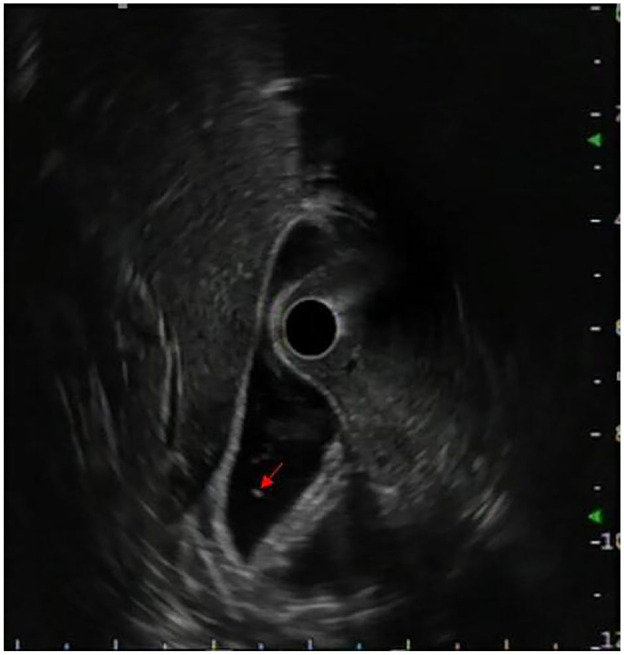

Case presentation: Our case report presents a case of a 23-year-old patient followed for Crohn disease in whom a diagnosis of acute pancreatitis induced by adalimumab was made. This diagnosis was confirmed after the elimination of other possible etiologies, and notably by the recurrence of pancreatitis after Adalimumab rechallenge. The occurrence of acute pancreatitis induced by TNFα inhibitors exposes to the risk of pancreatitis with other drugs in this class, hence the need to switch to another therapeutic class, which was Ustekinumab in our case.

Conclusion: Acute pancreatitis is an unusual complication of treatment with Adalimumab. Through our experience, based on solid scientific data, we want to draw the attention of clinicians to the reality of this complication. It should be considered in any patient on TNFα inhibitors who presents with acute pancreatitis without an obvious cause.